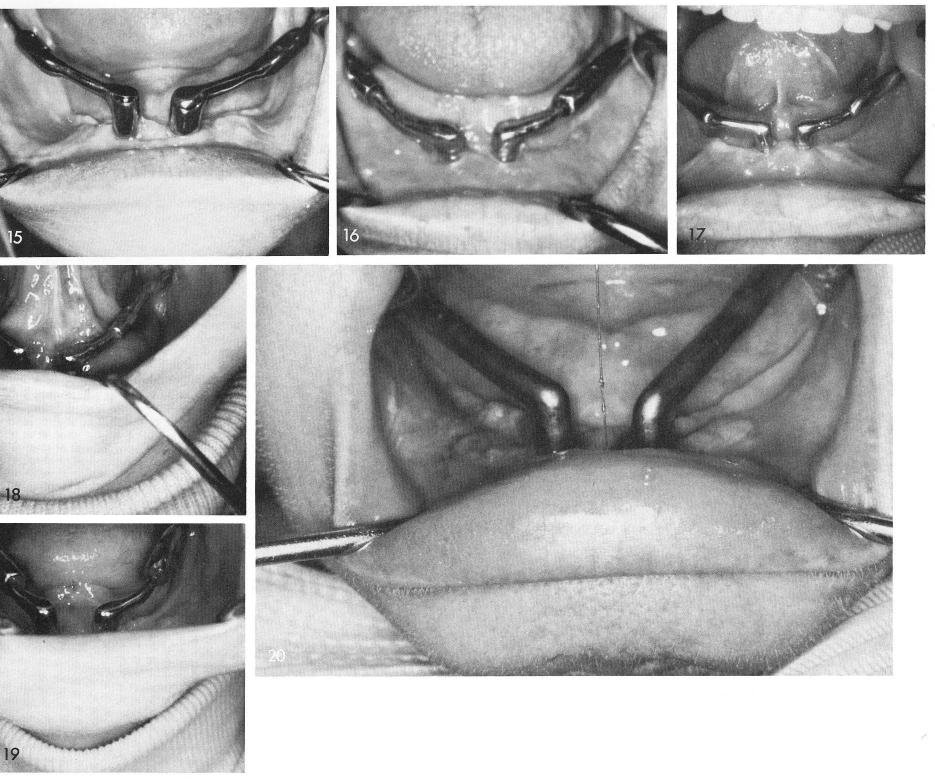

Mandibular Implants (published 1977)   Dr. Leonard I. Linkow